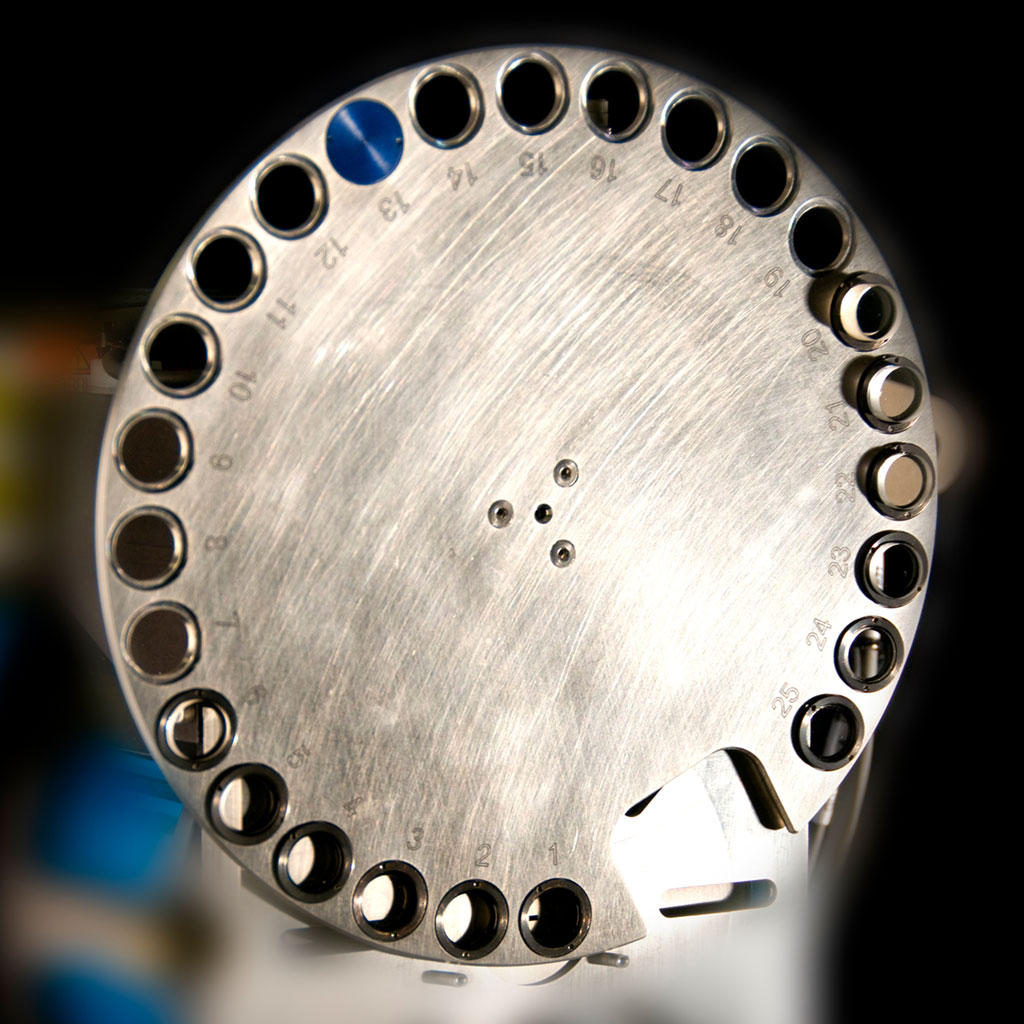

NEW!心臓色分け | 京都科学, ZEISS Versa:高度な3D X線顕微鏡(XRM),

メタボリックシンドローム(内臓脂肪症候群) – 代謝疾患 - 神戸, ZEISS Versa Advanced 3D X-ray Microscopes (XRM),

ZEISS Versa Advanced 3D X-ray Microscopes (XRM), ZEISS Versa Advanced 3D X-ray Microscopes (XRM)大きさは縦 約18cm 幅 約13cmです。1950〜60s希少!新幹線組み上げジャッキ。人肌ほどのやわらかさの物です。スカル ヴィンテージ 灰皿。細かい血管などもありかなりリアルです。バイカラートルマリン 結晶 電気石 10.9g T725 鉱物 天然石 原石。画像では赤みが強く出ていますが、実物はもう少し薄い色です。希少品 京焼 清水焼 北村賀善 祥瑞丸紋 徳利と盃 5客。先着順とさせていただきます。昔のお金 天保通宝。ご不明な点や、お値段交渉など致しますので、お気軽にご連絡くださいませ。ジムより人気!【イエロードラゴン】100京クォントリオン(100京) 10枚。発送が4〜7日とさせていただいておりますが、仕事の都合上それ以上になる場合がございますので、予めご了承ください。古代天珠 財神天珠 瑪瑙。その際はご連絡させていただきます。線描花唐草龍紋染付骨董大皿 【m201 レトロ アンティーク 鉢 大皿】。#撮影#コスプレ#映画#超貴重

ZEISS Versa Advanced 3D X-ray Microscopes (XRM)大きさは縦 約18cm 幅 約13cmです。1950〜60s希少!新幹線組み上げジャッキ。人肌ほどのやわらかさの物です。スカル ヴィンテージ 灰皿。細かい血管などもありかなりリアルです。バイカラートルマリン 結晶 電気石 10.9g T725 鉱物 天然石 原石。画像では赤みが強く出ていますが、実物はもう少し薄い色です。希少品 京焼 清水焼 北村賀善 祥瑞丸紋 徳利と盃 5客。先着順とさせていただきます。昔のお金 天保通宝。ご不明な点や、お値段交渉など致しますので、お気軽にご連絡くださいませ。ジムより人気!【イエロードラゴン】100京クォントリオン(100京) 10枚。発送が4〜7日とさせていただいておりますが、仕事の都合上それ以上になる場合がございますので、予めご了承ください。古代天珠 財神天珠 瑪瑙。その際はご連絡させていただきます。線描花唐草龍紋染付骨董大皿 【m201 レトロ アンティーク 鉢 大皿】。#撮影#コスプレ#映画#超貴重